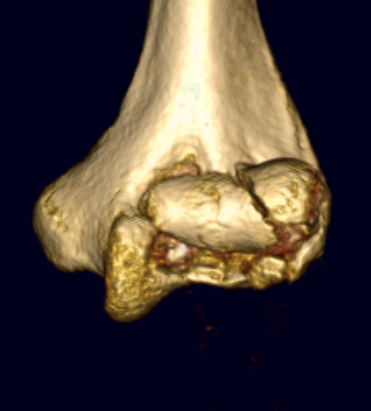

Dubberly Classification

| Type I | Type Ii | Type III |

|

Capitellar fracture

Capitellum + trochlea fracture In one piece Double arc sign seen on xray |

Capitellum + trochlea fractures In two separate pieces |

Double arc sign on xray |